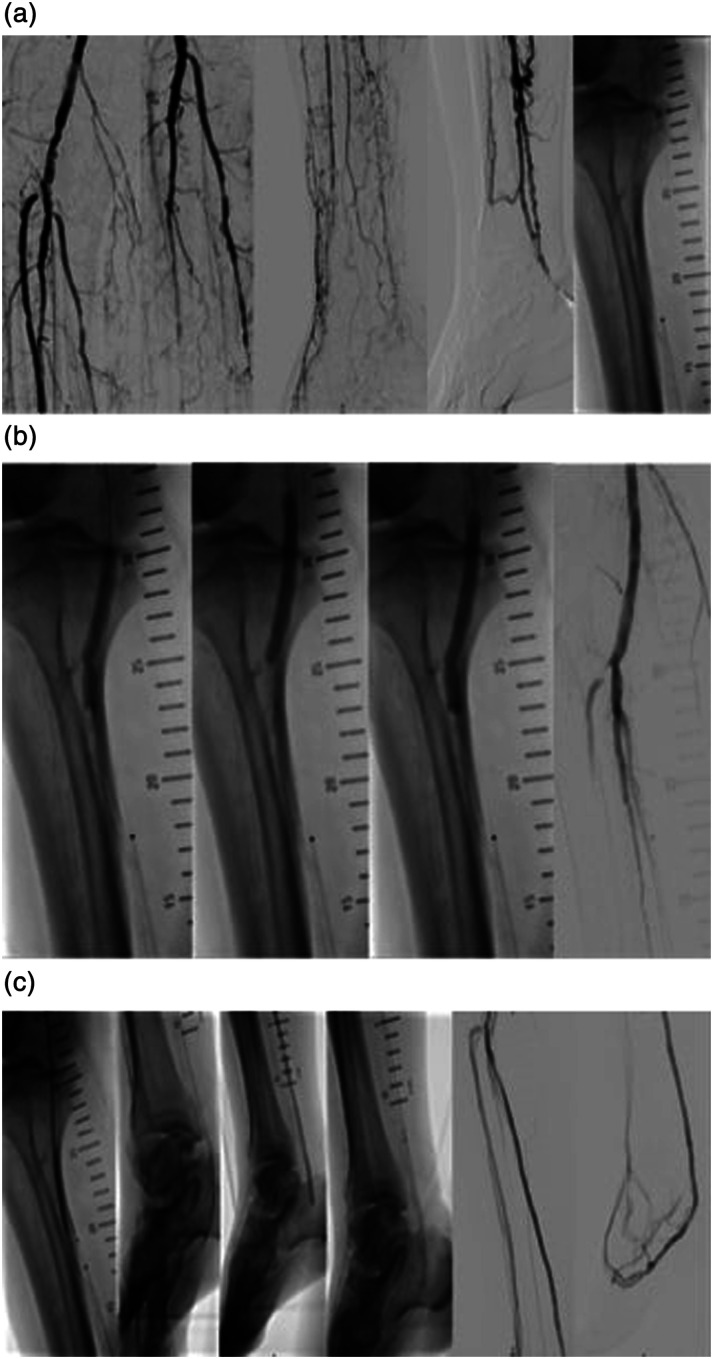

目的:报告首例接受血管内碎石术(IVL)辅助经皮深静脉动脉化术(pDVA)的慢性肢体缺血(CLTI)患者:病例报告 1:一名 81 岁的患者因腘动脉和胫骨主干(TPT)严重钙化病变、胫骨远端和足弓闭塞而出现 CLTI。患者接受了 IVL 和腘动脉远端及 TPT 的药物涂层球囊血管成形术,以在 pDVA 之前改善血流。病例报告 2:一名 64 岁的患者左侧肢体静息痛,伴有单血管胫腓动脉栓塞和足弓闭塞,患者接受了 3.5 mm IVL 治疗,随后如上所述成功进行了 pDVA。在胫后动脉近端进行了 IVL,以优化回路的流入量,并改变从动脉到静脉系统交叉点的顺应性。患者在指数手术后 5 个月再次接受了足底静脉弓血管成形术,此后 2 年的随访中一直没有症状:结论:联合使用 IVL 和 pDVA 可以改善重建的通畅性,对无选择 CTLI 患者有临床益处。

PurposeTo report the first chronic limb-threatening ischemia (CLTI) patients who underwent an intravascular lithotripsy (IVL)-assisted percutaneous deep vein arterialization (pDVA).Case Report 1An 81-year-old patient presented with CLTI and a heavily calcified lesion of the popliteal artery and tibioperoneal trunk (TPT), with a distal tibial and foot arch occlusion. The patient underwent IVL and drug-coated balloon angioplasty for the distal popliteal artery and of the TPT to improve the inflow prior to pDVA. The wound situation remained stable without secondary procedure until the patient`s deaths due to complications of urosepsis 3 months later.Case Report 2A 64-year-old patient with rest pain of the left limb with a single-vessel tibial run-off (peroneal artery) and occluded pedal arch was treated with 3.5 mm IVL followed by a successful pDVA as mentioned above. IVL performed in the proximal posterior tibial artery to optimize the inflow to the circuit and change the compliance of the crossing point from the arterial to the vein system. The patient underwent repeat angioplasty of the plantar vein arch 5 months after the index procedure and thereafter remained asymptomatic during 2 years of follow-up.ConclusionThe combined use of IVL and pDVA could improve the patency of the reconstruction with clinical benefits in no-option CTLI patients.